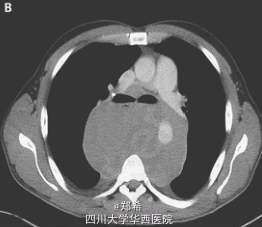

患者为30岁男性,2个月以来胸闷,气短,伴呼吸困难,吞咽困难,吞咽疼痛及体重下降14KG。3年前因I期精原细胞癌行睾丸切除术,术后失访。

心脏查体为窦性心率,并无杂音和奔马律,双肺听诊呼吸音清胸片以及CT发现后纵隔巨大包块。实验室检查发现人绒毛膜促性腺激素升高,为4miU/ml,正常<3。乳酸脱氢酶1400U/L(正常140-270)。甲胎蛋白正常。